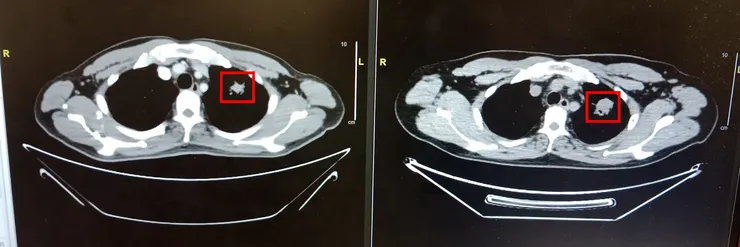

過去9個月其實也不是沒有好消息,2月的電腦斷層掃描(Computerised Tomography Scan),發現肺部的最大的癌細胞明顯縮小了約一半,肺裏其他細小的癌細胞也幾乎消失了。

左邊是2月,右邊是去年拍的,可以見到紅框中的百點(癌細胞)小了約一半